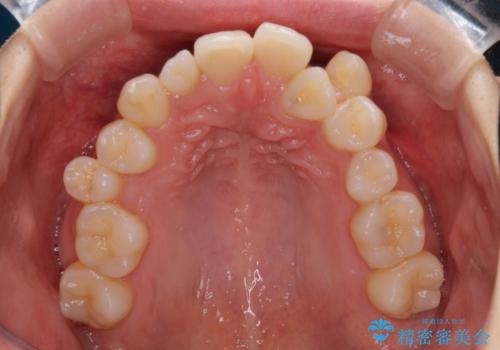

補助装置を併用したインビザラインでの八重歯の抜歯矯正

- 八重歯と奥歯の咬み合わせを気にして来院された患者様です。

インビザラインによる矯正治療を希望されたため、八重歯改善のための抜歯矯正部分は補助装置を併用し、その後はインビザラインにて行うこととしました。

下顎の右側変位が顕著であったため、ワイヤー矯正の方が咬み合わせは改善しやすいのですが、ある程度は時間がかかっても良いとのことであったので、インビザラインにて矯正治療を行うこととしました。

骨格的に下顎が右側に変位していたため、上下正中を合わせることは困難であることは分かっていました。それでも、なるべく合わせるようにとしたため、治療期間は長期間となりました。

長期間とはなりましたが、咬み合わせが改善され、患者様には大変満足していただきました。